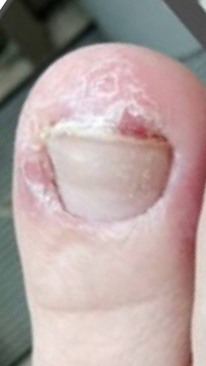

Онихолизис

После полученной механической травмы и образования субнегтевой гематомы произошло отслоение ногтя (онихолизис). Новая ногтевая пластина стала образовываться неправильно и кожный валик мешал её прорастанию.

Назначено: Зачистка ногтя у подолога, 2 процедуры 1 р/мес; ФДТ с ФС REVIXAN Derma PRO - 5 процедур 1 раз в 3-5 дней.